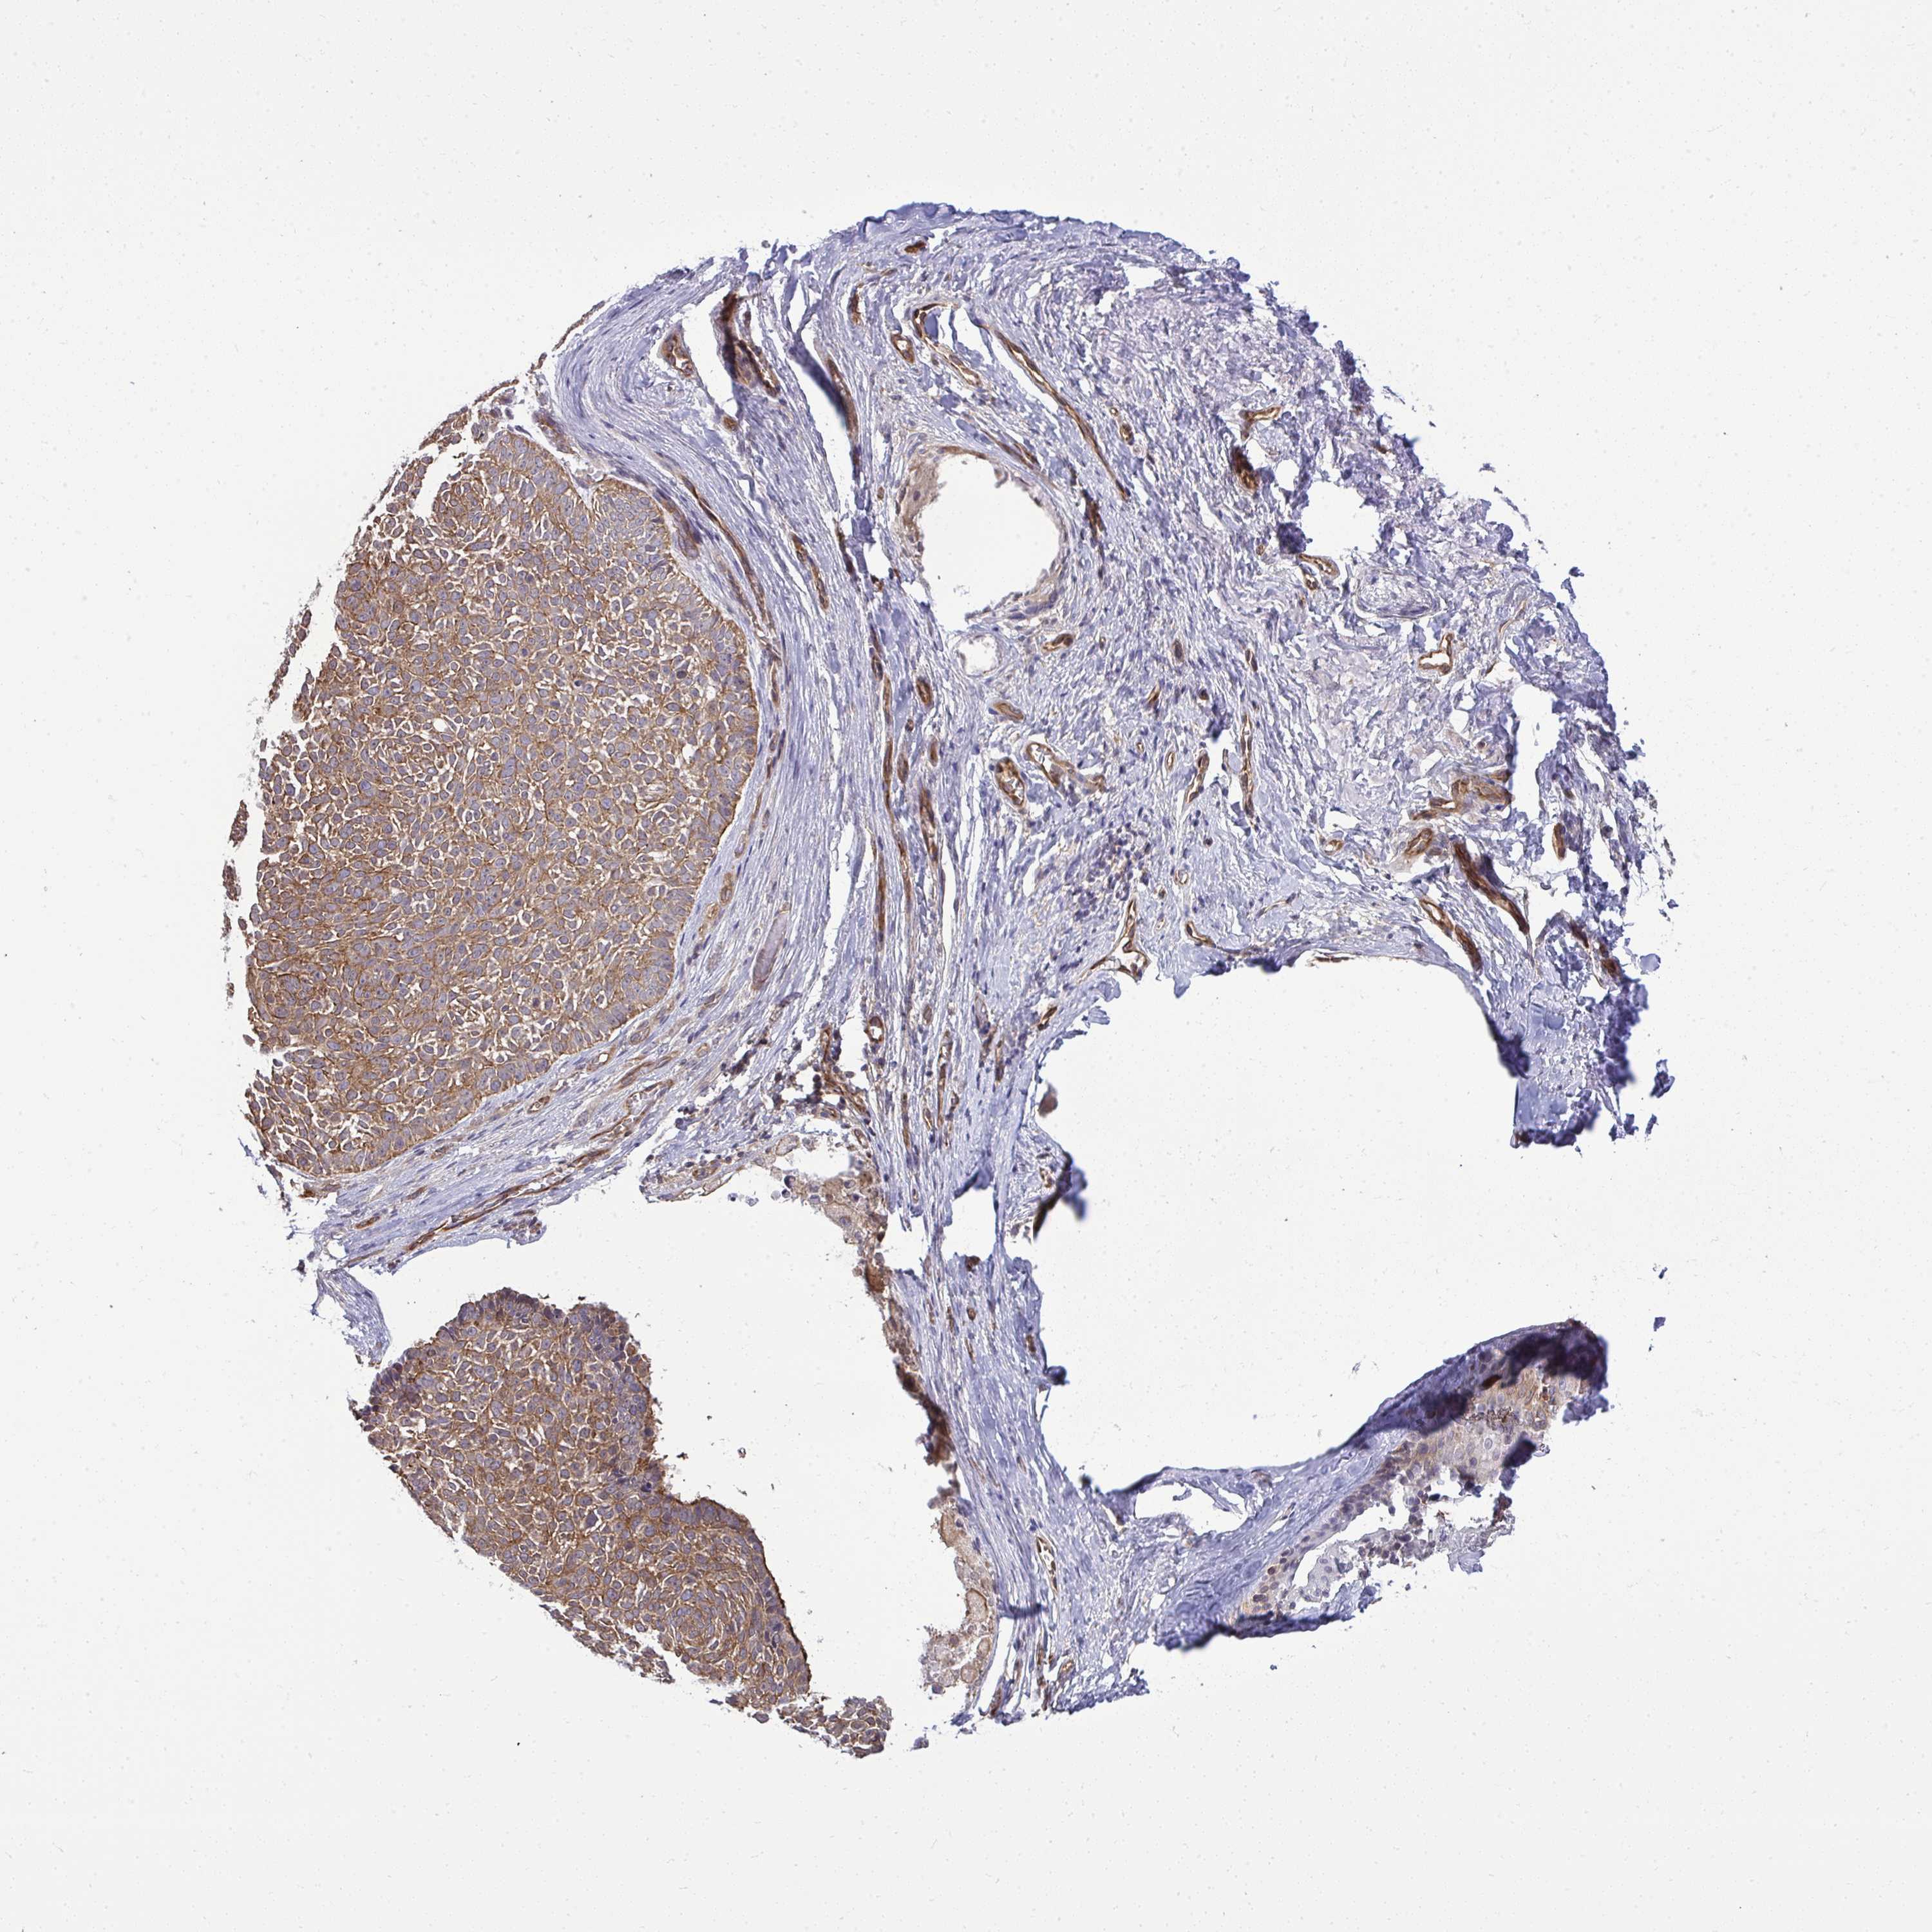

SKIN CANCER - Protein expressioni

A mouse-over function shows sample information and annotation data. Click on an image to view it in a full screen mode. Samples can be filtered based on level of antibody staining by selecting one or several of the following categories: high, medium, low and not detected. The assay and annotation is described here.

Antibody stainingi

Antibody staining in the annotated cell types in the current human tissue is reported as not detected, low, medium, or high, based on conventional immunohistochemistry profiling in selected tissues. This score is based on the combination of the staining intensity and fraction of stained cells.

Each image is clickable and will lead to virtual microscopy that enables deeper exploration of all samples and also displays staining intensity scores, fraction scores and subcellular localization as well as patient and tissue information for each sample.

Antibody HPA053970

Antibody HPA058655

Staining

High

Medium

Low

Not detected

Intensity

Strong

Moderate

Weak

Negative

Quantity

>75%

75%-25%

<25%

None

Location

Nuclear

Cytoplasmic/membranous

Cytoplasmic/membranous,nuclear

Basal cell carcinoma

Squamous cell carcinoma, NOS